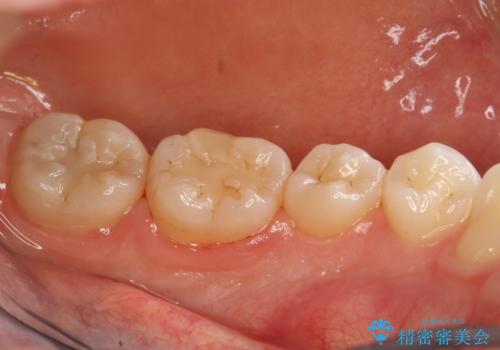

半年ぶりのPMTC

- 半年ぶりの来院で、クリーニング希望とのことでした。PMTC30分コースを行いました。

虫歯や歯周病を予防するには、歯垢をしっかり落とすことが大切です。

特に奥歯周辺はハブラシが入りにくく磨き残しの多いところです。毎回の磨き残しを放置せず、定期的に機械的なクリーニングを行うことが大切です。